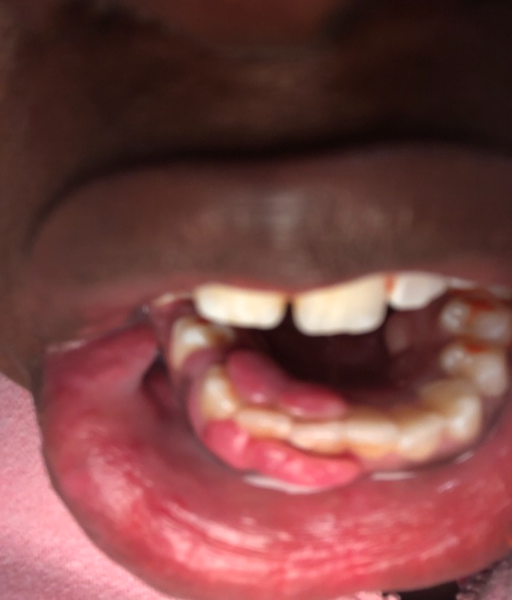

I have an open bite due to a tongue thrust I've had since I was a baby (I'm 22 now). My open bite has caused some issues like with trouble chewing, I have a slight lisp when I talk, I hate my smile and sometimes I find myself gasping for breath in my sleep. Also, my tongue thrust has gotten so intense that my top teeth are starting to hurt because of me pushing on them in my idle time or when I'm asleep. I began looking into Orthognathic Surgery and I think it's something I want to do but I also want to know outside of it closing my open bite and realigning my jaws, will it correct my tongue thrust?

I have an open bite due to a tongue thrust I've had since I was a baby (I'm 22 now). My open bite has caused some issues like with trouble chewing, I have a slight lisp when I talk, I hate my smile and sometimes I find myself gasping for breath in...